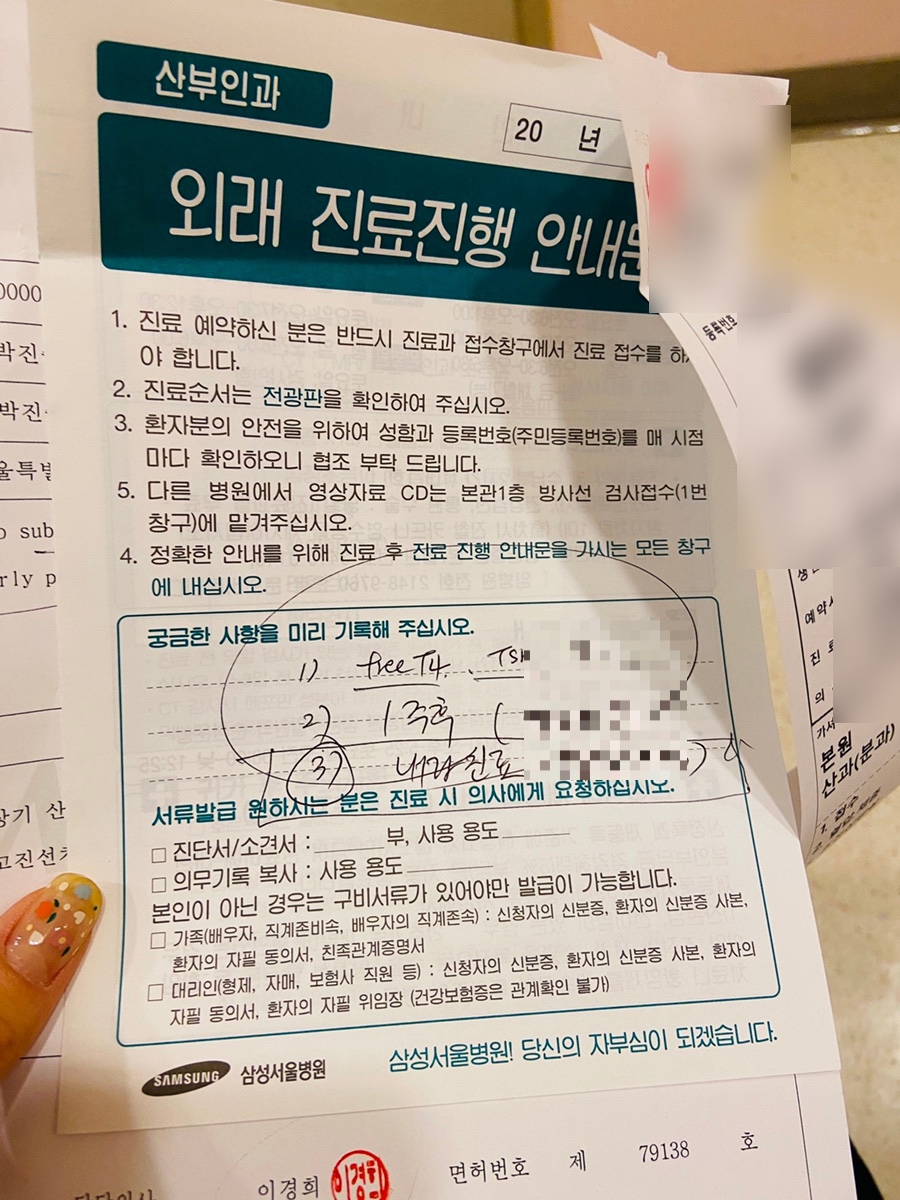

남편에게 전화해서 의논을 했는데… 동네병원에 가지 말고 삼성병원으로 오라고 했어요.남편이 삼성병원에서 일하니까.. 전부터 삼손에 와서 분만은 하라고 했거든요. 어쨌든 삼손병원에 갈 수 있도록 진료의뢰서를 써 달라고 했어요.

그리고 남편이 다음 날 삼성병원 산부인과 외래진료도 잡아줬어.요~

다음 날… 8주 4일째 되는 날이었습니다서울 삼성병원 산부인과 진료를 다녀왔어.요~

오수영 선생님께 진료를 받았습니다.오수영 교수님이 너무 친절하고 설명도 잘한다고 권유해서 갔습니다. 너무 친절하고 설명도 잘하셨어요.:)

초음파를 봐 주시는 선생님도 친절하셔서 참 다행이라고 생각을 합니다.~~

TSH 수치랑 다른 수치 몇 개 보는 거야 피 몇 통 뽑고 왔어요 ㅜㅜ

진찰료, 피검사료, 초음파 진단료까지 해서 47,000원 정도인데, 직원 가족 할인으로 33,000원 정도!!

대학병원에서 분만하는 산모분들도.. 대학병원의 진료비가 비싸다고 해서 조금 후에 귀가하는 사람도 있는 것 같은데… 오히려 일반동네병원보다 비싸지 않아서 깜짝 놀랐어요.(할인전 금액으로 비교해도 동네병원보다 저렴)